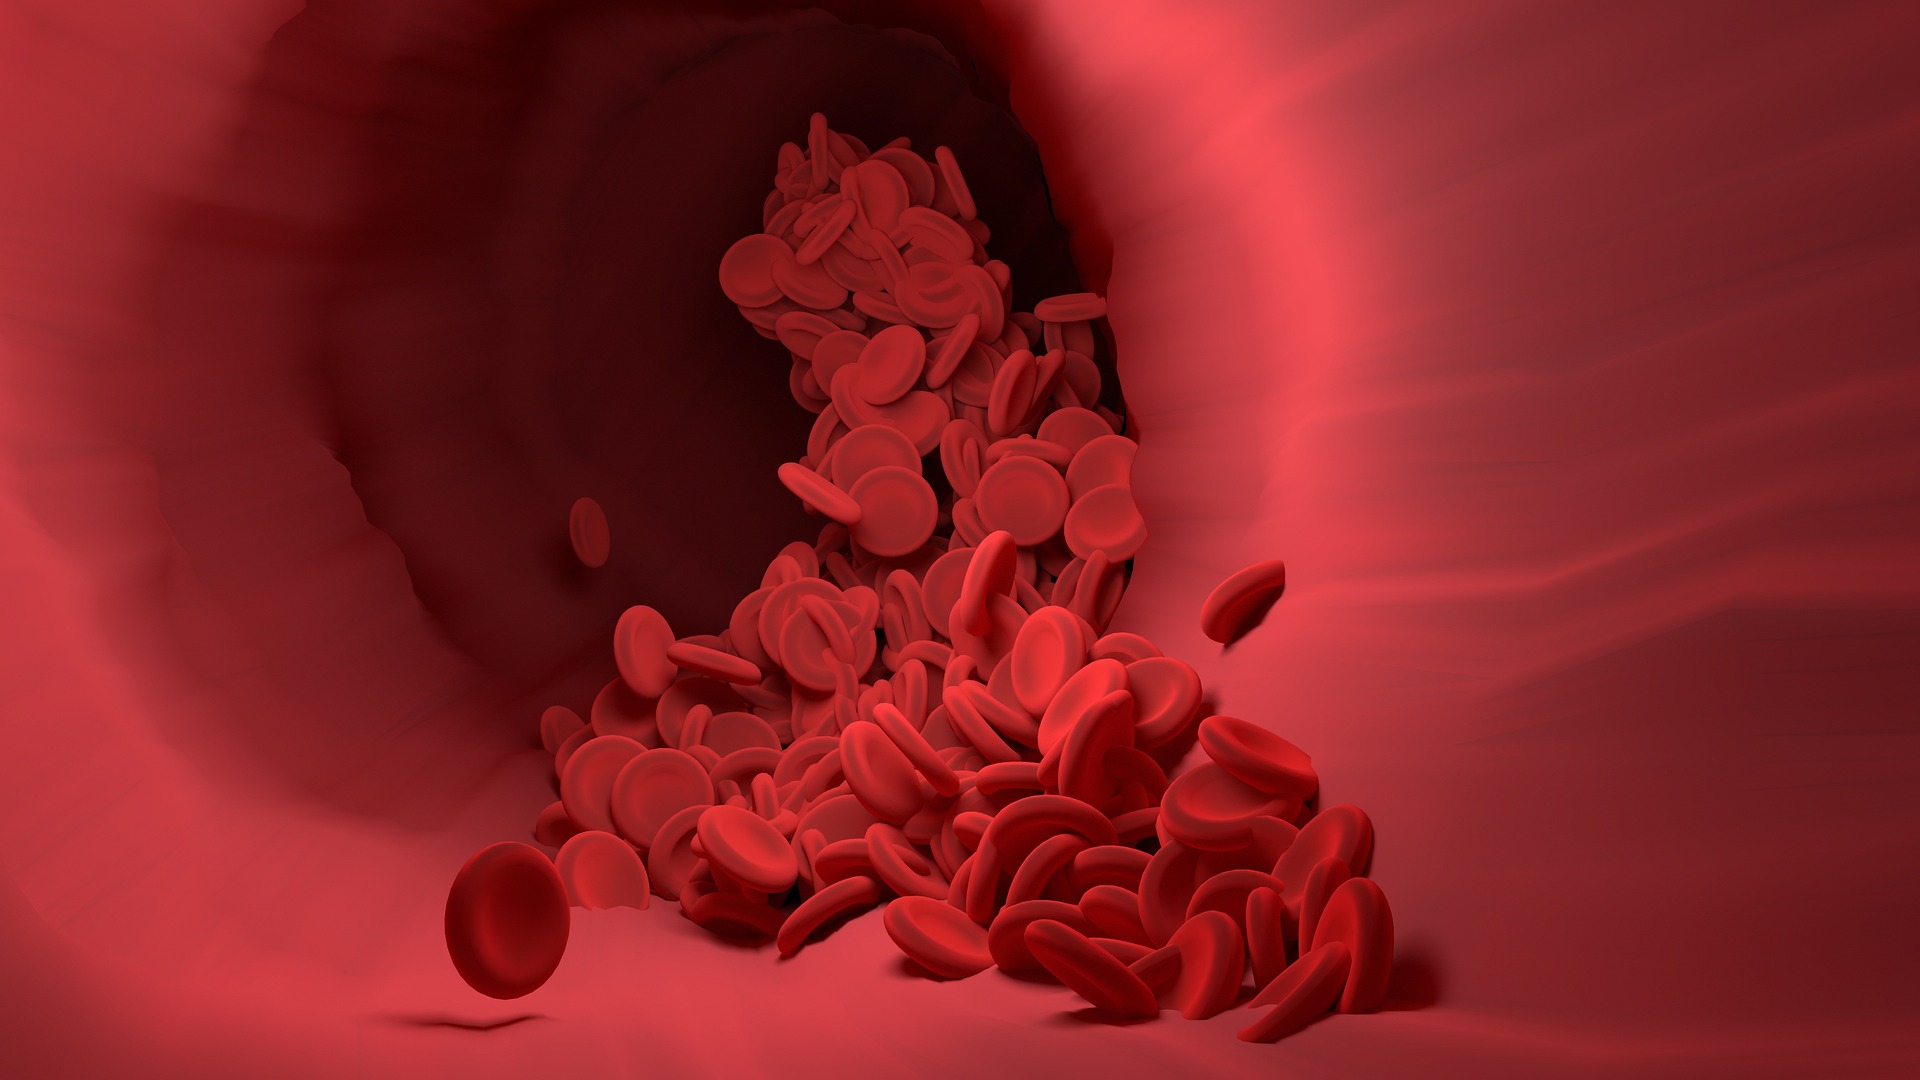

뇌졸중(중풍)은 온몸의 신경이 모인 뇌혈관이 막히거나 터져서 발병하며,

뇌혈관이 막히는 것을 뇌경색, 뇌혈관이 터지는 것을 뇌출혈이라 합니다.

정상인의 혈액을 혈맥분석기로 보면,

혈액이 동글동글하고 점점이 ‘기’가 많이 박혀 있어 활발하게 움직입니다.

그런데 중풍 환자의 피를 보면 혈구 모양이 동그랗지 않고 어혈과 불순물이 많습니다.

섬유질 같은 지방 덩어리, 콜레스테롤 덩어리 등 찌꺼기가 많아

혈액이 끈적끈적하고, ‘기’도 활발하지 않습니다.

즉, 정상인은 온몸의 기와 혈이 잘 순환되지만,

중풍 환자는 기와 혈이 뭉쳐서 순환이 잘 이루어지지 않습니다.